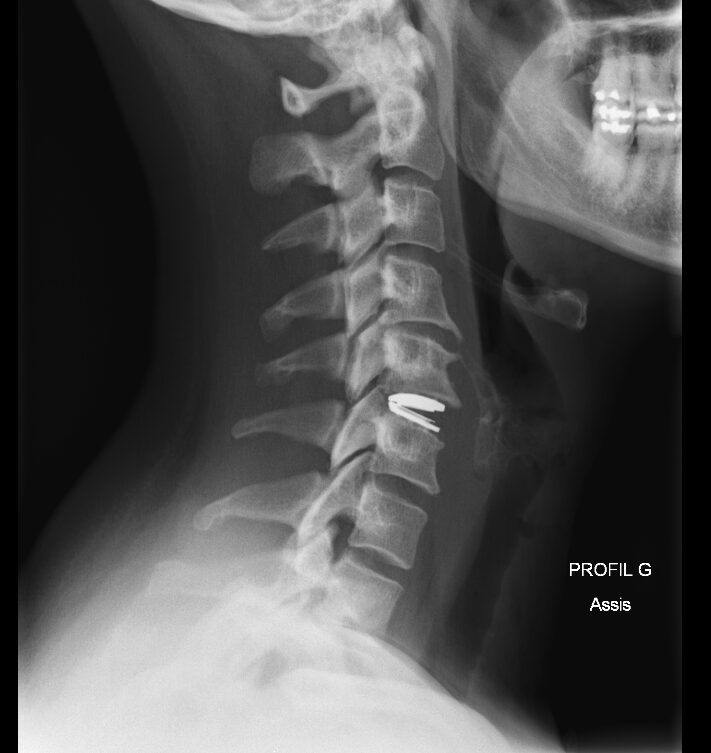

Ensuite le patient bénéficie d’une radiographie de contrôle le lendemain de l’intervention et peut retourner à domicile par la suite.

radio de controle